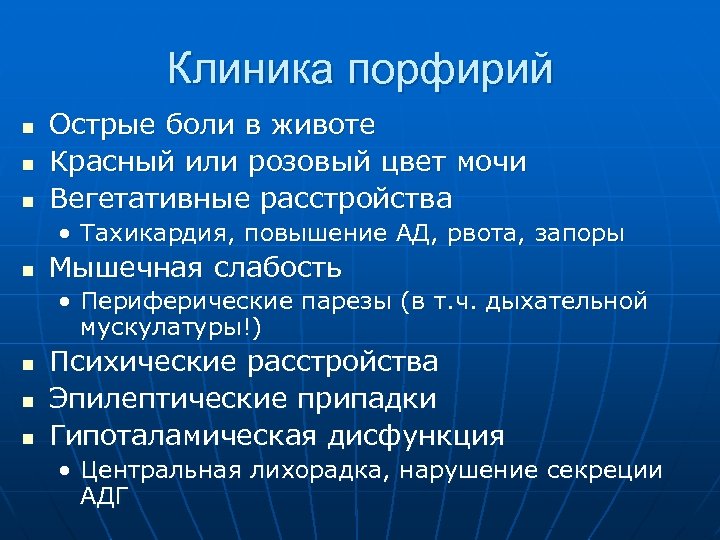

Клиника порфирий n n n Острые боли в животе Красный или розовый цвет мочи Вегетативные расстройства • Тахикардия, повышение АД, рвота, запоры n Мышечная слабость • Периферические парезы (в т. ч. дыхательной мускулатуры!) n n n Психические расстройства Эпилептические припадки Гипоталамическая дисфункция • Центральная лихорадка, нарушение секреции АДГ